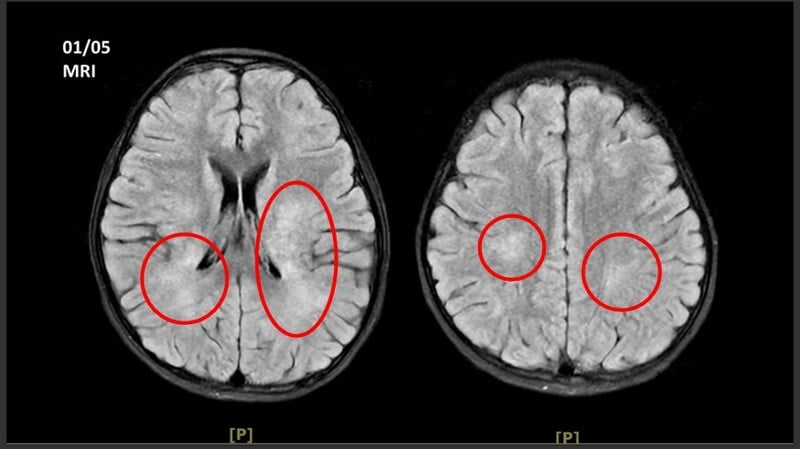

王傳育主任指出,女童當時血壓明顯偏高,心跳也較慢,醫療團隊擔心已有腦壓升高或顱內病變,立即安排住院,並同步給予降低腦壓治療與核磁共振掃描。檢查結果顯示,小腦、視丘及大腦白質、皮質下都可見異常訊號,符合急性散播性腦脊髓炎的影像表現。